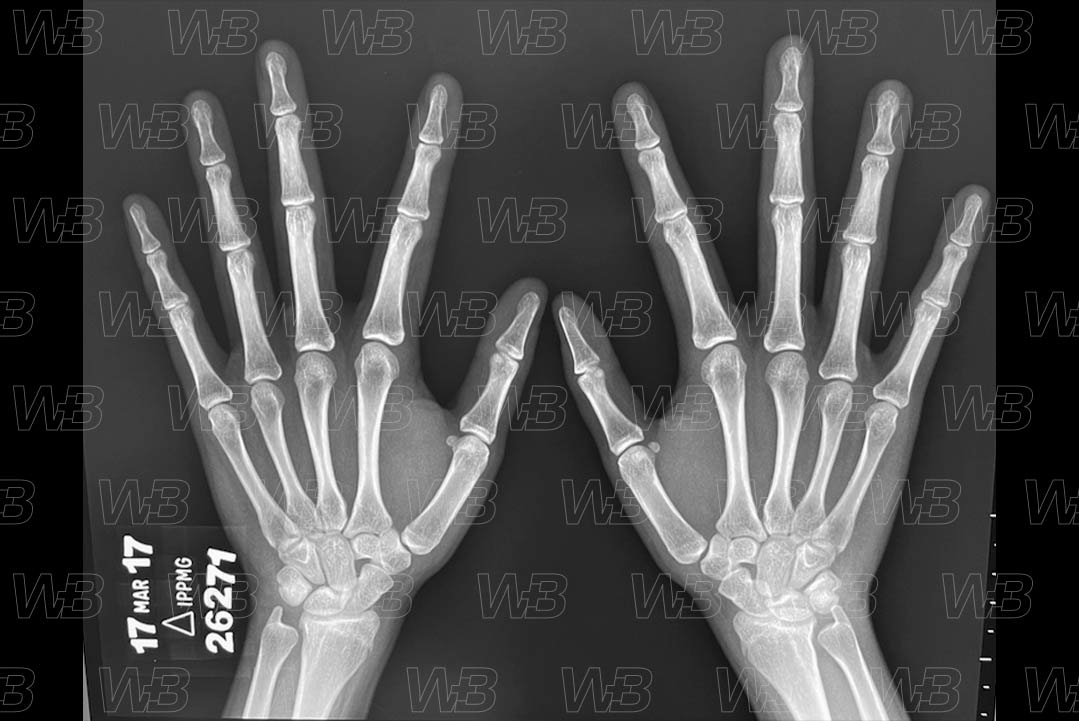

Atlas idade óssea - Feminino - 17 anos

RADIOGRAFIA MÃOS E PUNHOS (IDADE ÓSSEA) [cms-watermark]

Feminino

17 anos:

• Fusão completa das epífises do rádio e ulna.